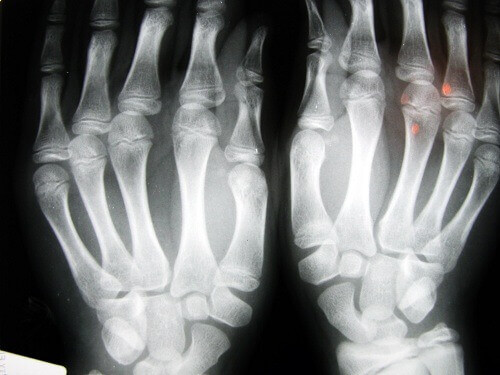

Mange lurer på om det å knekke fingrene eller andre ledd kan lede til leddgikt. Realiteten er at om det er en daglig uvane over mange år, kan brusken skades.

En av de best kjente studiene i forhold til dette ble gjennomført av Dr. Donald Unger, som i mer en 60 år knakk fingrene på sin venstre hånd to ganger om dagen, men ikke på sin høyre hånd. Hvert år undersøkte han hendene sine, uten å finne tegn til degenerative sykdommer, selv i venstre håden som han knakk fingrene på hver dag.

En annen studie observerte 30 eldre mennesker ved et eldrehjem i Los Angeles. De som hadde knekket fingrene hele livet hadde ikke utviklet artrose. I en tredje studie utført blant 45-åringer i Detroit konkluderte forskerne at hovedproblemet var manglende gripestyrke og at 80% av de som deltok i studien hadde hevelse i fingrene.

Det er disse resultatene som gjør at vi ikke anbefaler at du knekker fingrene for ofte. Selv om en gang i blant for å lindre stivhet er mest sannsynlig ikke helseskadelig.